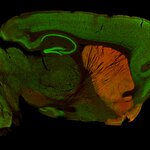

IHC: 1 : 500 gallery

Functionally, DAT contributes to the termination of DA signaling by reuptaking DA, thereby controlling both the duration and magnitude of dopaminergic transmission (4). It is predominantly found in dopaminergic neurons and enriched in regions such as the striatum, substantia nigra, and ventral tegmental area, which are associated with motor control and reward mechanisms (5).